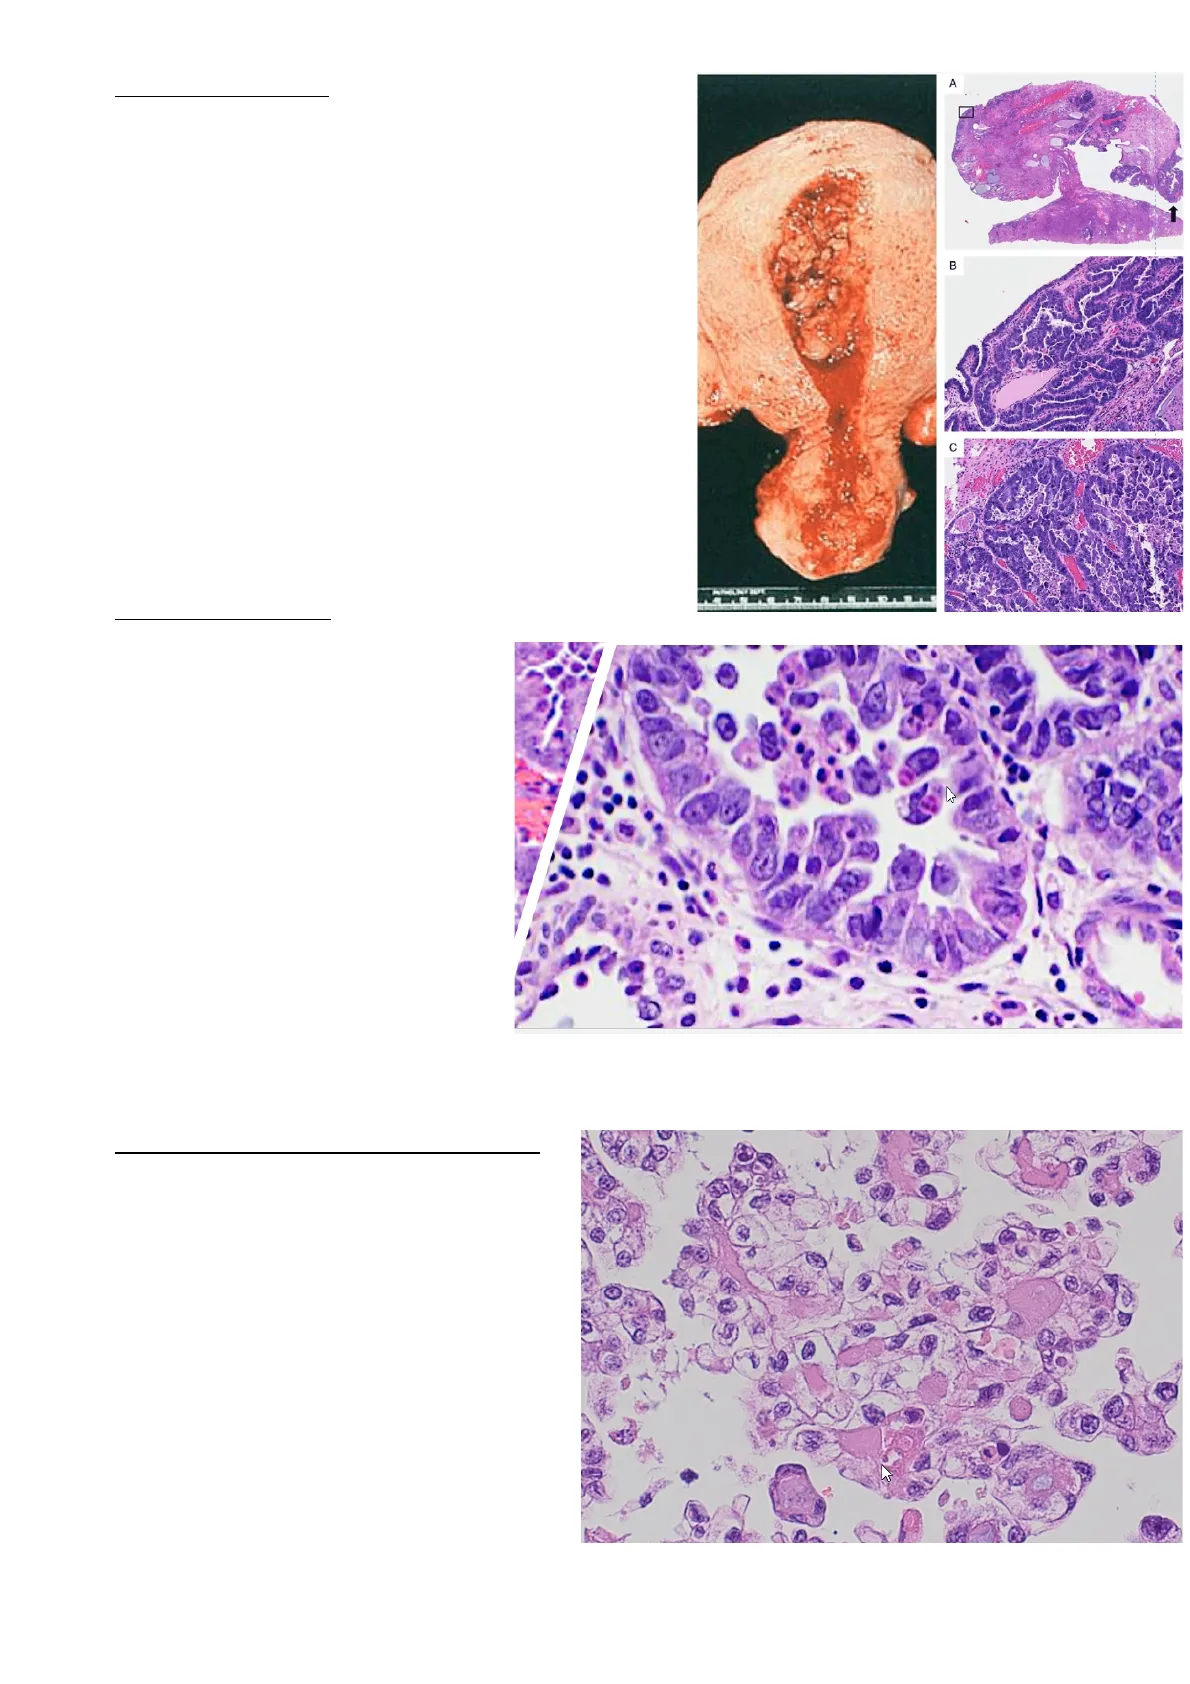

L'aspetto macroscopico è variabile, tendenzialmente si presenta come una neoformazione endometriale polipoide; a volte può insorgere nel contesto di un polipo endometriale glandulo- cistico. Nell'immagine a sinistra, si vede la formazione che affiora nella cavità endometriale, mentre nell'immagine A vediamo un polipo glandulo-cistico, che è espressione di un endometrio inattivo, con un carcinoma sieroso. A 1 B C

L'endometrio è inattivo, mentre la lesione è caratterizzata da strutture ghiandolari- papillari (raramente ghiandolari e più spesso papillari) composte da:

Tutte queste caratteristiche indicano, per definizione, un carcinoma ad alto grado. Nell'immagine a dx vediamo le cellule hobnail cioè a "testa di chiodo", pronte a esfoliare e diffondere nella cavità endometriale e, attraverso le tube, nel peritoneo. Quindi, la malattia ha una elevata propensione a diffondere per via peritoneale.

p53 Il carcinoma sieroso è il secondo istotipo di carcinoma dell'endometrio per frequenza dopo l'adenocarcinoma endometrioide. Rappresenta il 10-15% dei casi ma è responsabile del 40% dei decessi per cancro dell'endometrio, perciò è sicuramente un istotipo aggressivo. Da un punto istologico, il carcinoma sieroso non forma ghiandole a differenza dell'adenocarcinoma endometrioide, ma forma strutture a pattern papillare come vediamo nell'immagine; quindi, il carcinoma sieroso cresce in papille e micropapille. Le cellule neoplastiche sono caratterizzate da un'atipia di grado severo a causa dell'elevato pleomorfismo nucleare. Le mitosi sono numerose. Dal punto di vista immunoistochimico, il carcinoma sieroso è caratterizzato da un'alterazione dell'espressione di p53, presente nel 99% dei casi: p53 mutata può essere iperespressa o può essere null, ovvero completamente assente. Inoltre, il carcinoma sieroso dell'endometrio ricorda il carcinoma sieroso di alto grado tubo-ovarico peritoneale, che vedremo essere molto simile anche molecolarmente.